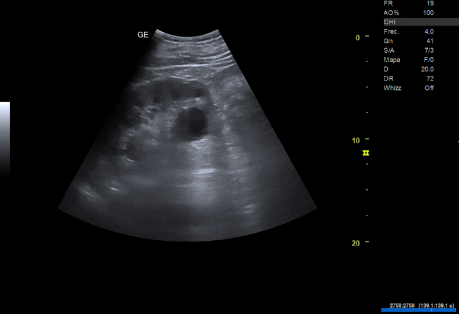

- Ecografía clínica renovesical: Vejiga sin lesiones ocupantes de espacio, sin residuo postmiccional, próstata de tamaño aumentado (56 cc). Ambos riñones con quistes corticales simples, de hasta 9,6 cm en el riñón izquierdo. Sistema excretor derecho no dilatado. Leve-moderada dilatación pielocalicial izquierda. No se evidencian imágenes ecográficas sugestivas de litiasis en pelvis renal.

- Resonancia magnética renal con contraste: hidronefrosis grado II izquierda, secundaria a litiasis obstructiva de 5 mm localizada en el tercio inferior del uréter, inmediatamente caudal al cruce con los vasos ilíacos. Quistes sinusales y simples corticales bilaterales, el mayor de 9,4 cm de eje craneocaudal en el polo inferior del riñón izquierdo. Resto sin alteraciones significativas.